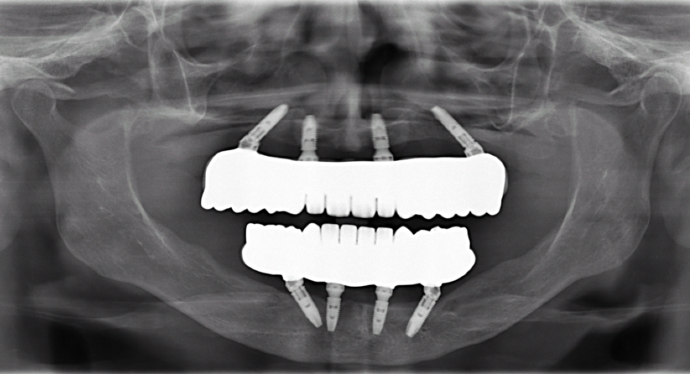

All-on-4/ Full Mouth Dental Implants / Teeth in a Day: Case 12-HM-Upper and lower All-on-4 bridges

This healthcare professional unfortunately had gum disease early on in her life and was given a top denture and was unhappy with her lower partial. She was trying to hold on to the very last tooth to avoid wearing a lower denture. She had consulted many doctors who told her that she had no bone for dental implants and would need major bone grafting procedures. Dr. Bidra identified areas of available bone using a CT scan, and successfully performed the All on 4 procedure on upper and lower (top and bottom) without the need for any bone grafting, and gave her fixed permanent zirconia bridges.

Procedures : extractions, implants, All on 4 , Teeth in a day, no bone grafting and full mouth reconstruction with monolithic zirconia bridges.